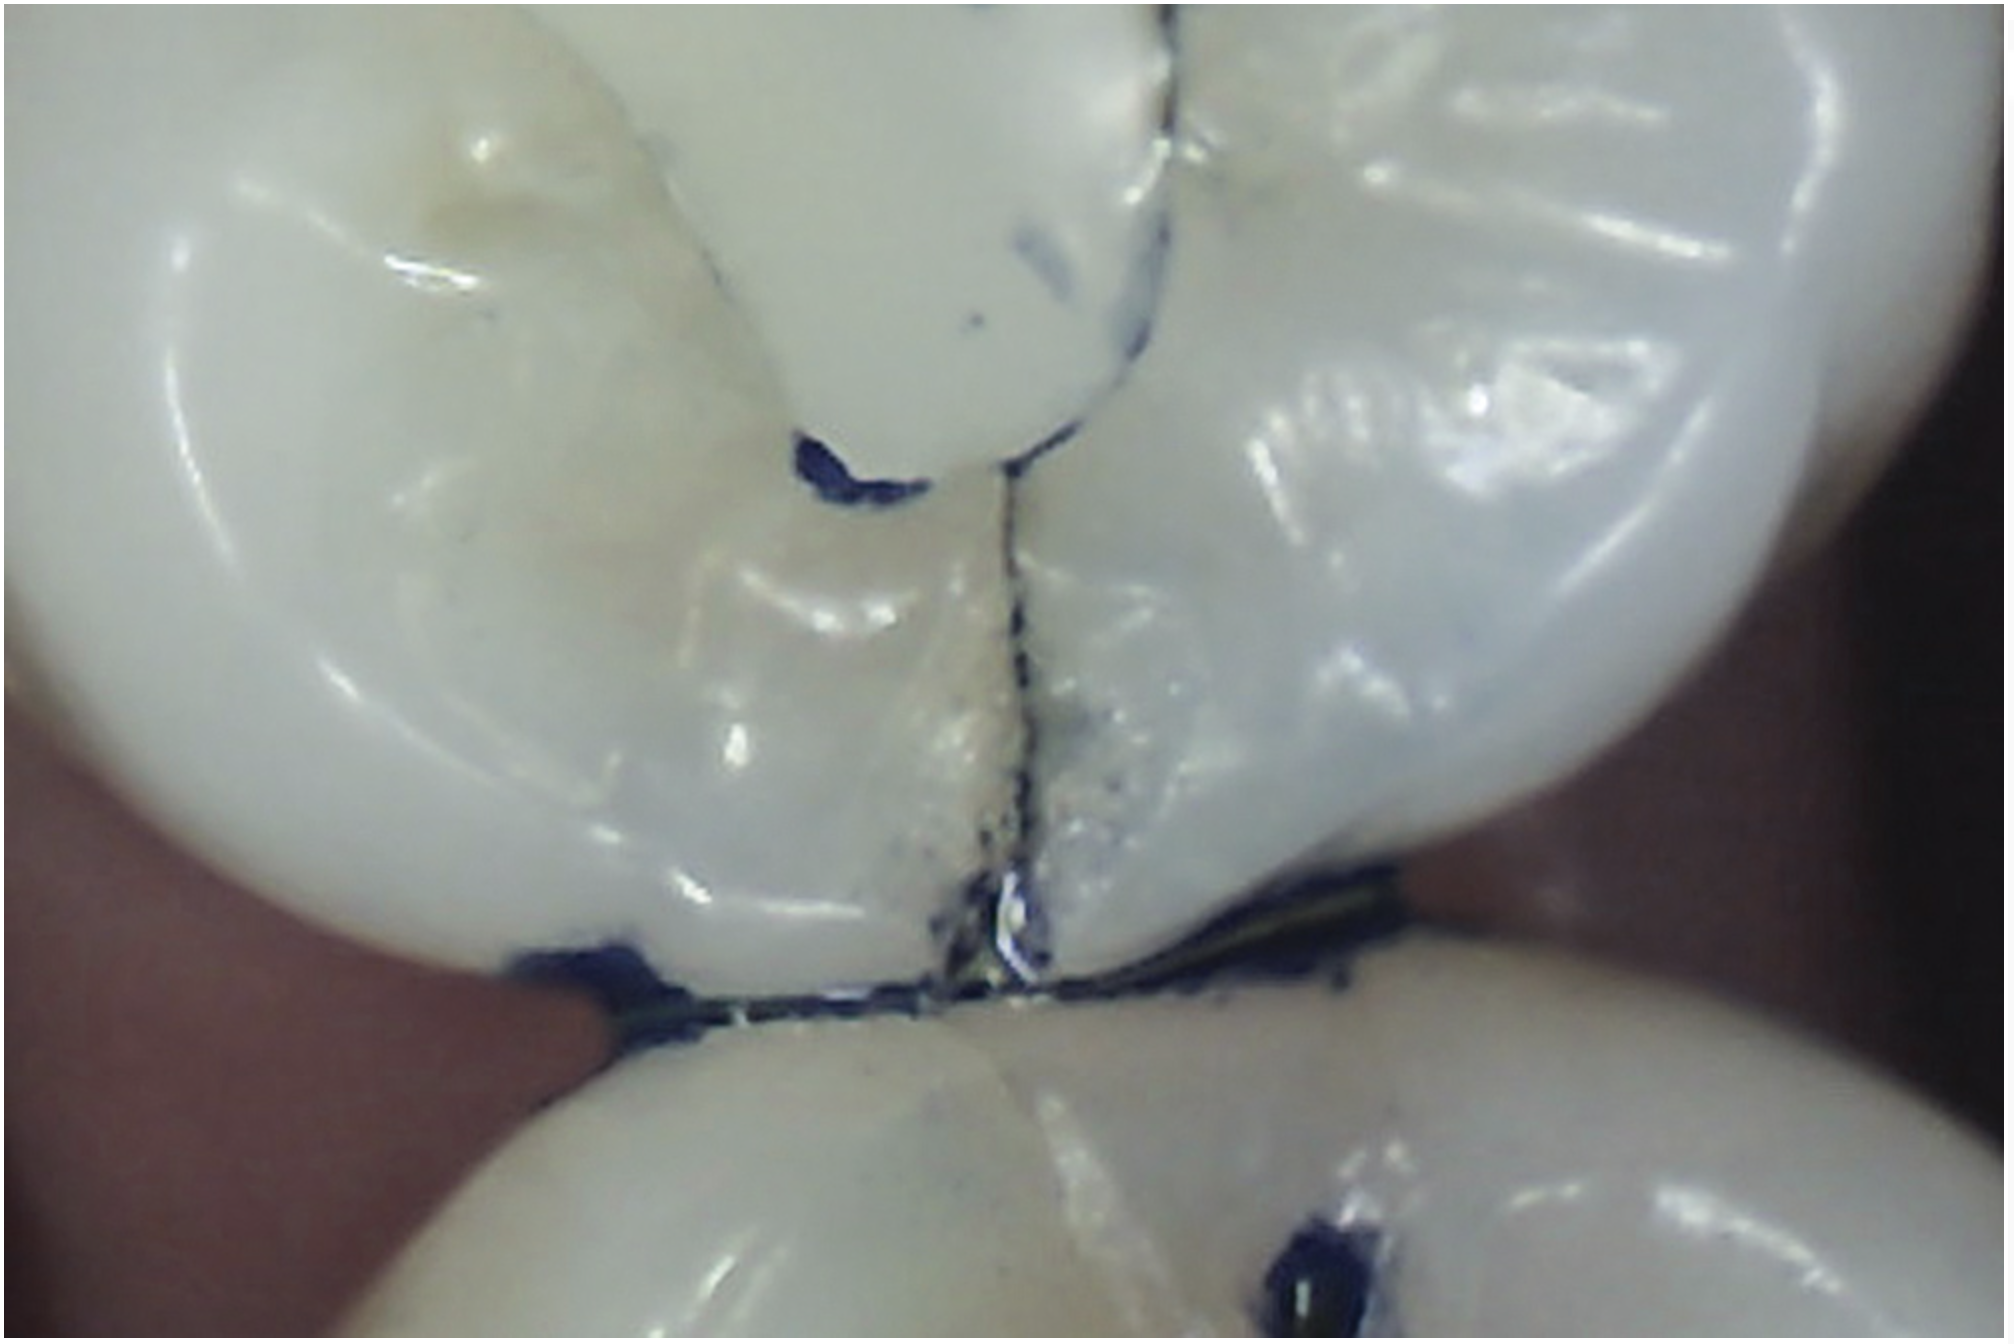

Staining

Methylene blue dye is the most commonly used dye to stain cracks because of its pooling tendency.2,3,14,16,17,23 The dye pools into the enamel and dentin cracks and the tooth is thoroughly rinsed. The resulting dark stain retained in the crack lines then helps enable cracks to be detected (Figure 4 and Figure 5). Methylene blue dye, however, also stains dental plaque, requiring the tooth surface to be cleaned with pumice or prophylaxis paste before dye application.14 The dye also can be absorbed by dentin, but any residual dye can be removed using a 10-second phosphoric acid etch.14 A comparative study of dye staining and transillumination concluded that methylene blue dye staining and transillumination performed simultaneously is the optimal crack assessment technique.23

Fig 4. Subtle asymptomatic occlusal crack (arrow) of a mandibular right second molar (occlusal view).

Figure 4

Fig 5. Methylene blue dye staining further revealing the occlusal extent of the crack shown in Fig 4.

Figure 5